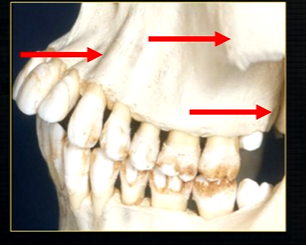

what can you say about the surface anatomy of the maxilla around the teeth themselves?

very undulating - prominences over roots

bony spike of the anterior nasal spine

becomes visible at the side view

posteriorly, the maxilla….

widens as it articulates with the zygoma or cheekbone

The zygomatic buttress is a key vertical support structure of the midface, formed by the junction of the zygomatic process of the maxilla and the zygomatic bone

bulk/prominence of the zygomatic cheekbone - radiographically this can overly the apical tissues of the upper molar teeth - solid, dense, white shadow

if its hollowed out by the maxillary sinus, it casts a white, radiopaque U shaped shadow - radiolucent centre

what is the canine prominence?

bony undulation over the canine root that is especially prominent